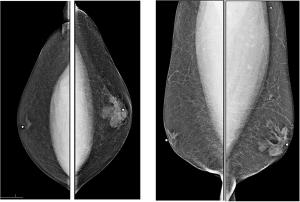

Case History: 54-year-old male presents with palpable right retroareolar abnormality.